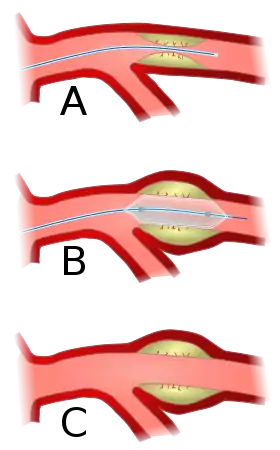

Angioplasty, also known as balloon angioplasty and percutaneous transluminal angioplasty (PTA), is a minimally invasive endovascular procedure used to widen narrowed or obstructed arteries or veins, typically to treat arterial atherosclerosis.[1] A deflated balloon attached to a catheter (a balloon catheter) is passed over a guide-wire into the narrowed vessel and then inflated to a fixed size.[1] The balloon forces expansion of the blood vessel and the surrounding muscular wall, allowing an improved blood flow.[1] A stent may be inserted at the time of ballooning to ensure the vessel remains open, and the balloon is then deflated and withdrawn.[2] Angioplasty has come to include all manner of vascular interventions that are typically performed percutaneously.

Access to the vascular system is typically gained percutaneously (through the skin, without a large surgical incision). An introducer sheath is inserted into the blood vessel via the Seldinger technique.[17] Fluoroscopic guidance uses magnetic resonance or X-ray fluoroscopy and radiopaque contrast dye to guide angled wires and catheters to the region of the body to be treated in real time.[18] Tapered guidewire is chosen for small occlusion, followed by intermediate type guidewires for tortuous arteries and difficulty passing through extremely narrow channels, and stiff wires for hard, dense, and blunt occlusions.[19] To treat a narrowing in a blood vessel, a wire is passed through the stenosis in the vessel and a balloon on a catheter is passed over the wire and into the desired position.[20] The positioning is verified by fluoroscopy and the balloon is inflated using water mixed with contrast dye to 75 to 500 times normal blood pressure (6 to 20 atmospheres), with most coronary angioplasties requiring less than 10 atmospheres.[21] A stent may or may not also be placed.

At the conclusion of the procedure, the balloons, wires and catheters are removed and the vessel puncture site is treated either with direct pressure or a vascular closure device.[22]